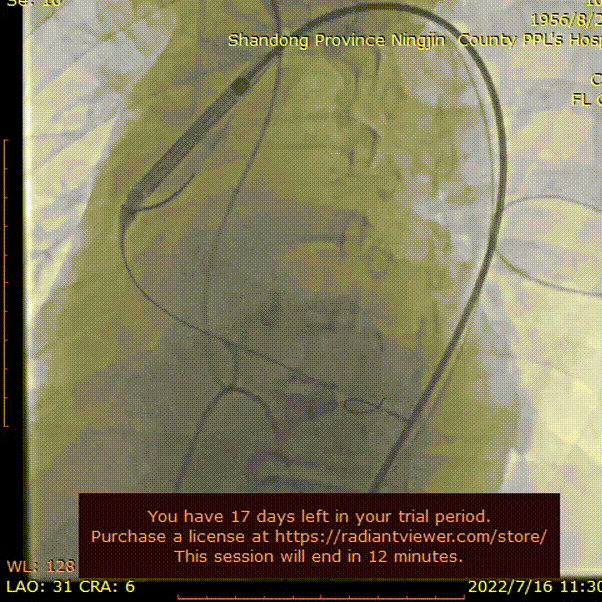

外周血管及主动脉弓解剖

双侧血管内径良好,所见腹主动脉血管壁钙化形成

双侧血管内径良好,所见主动脉血管壁钙化形成